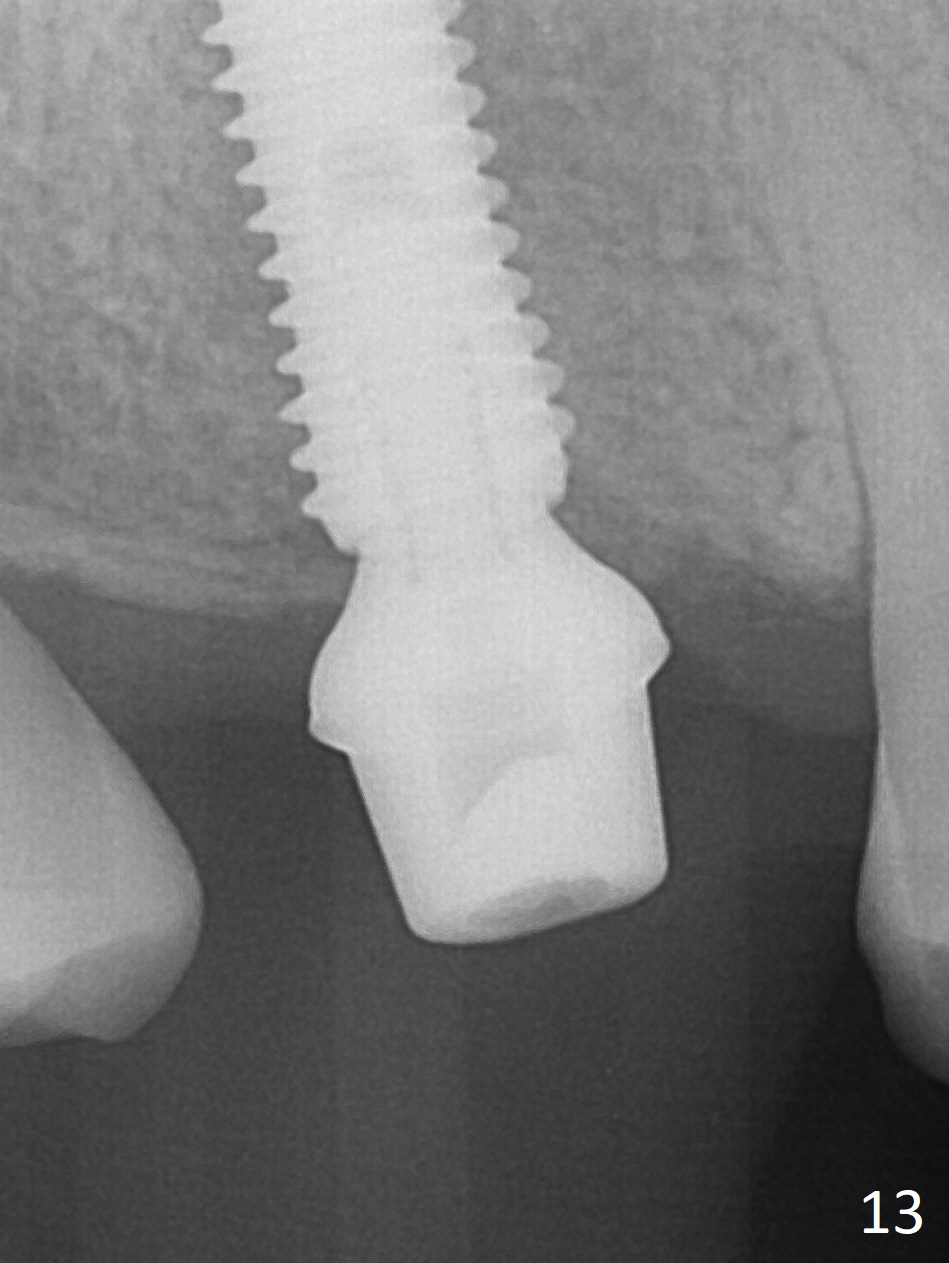

The palatal cusp of the affected 2nd premolar is apparently rotated distal (Fig.1). It is more obvious for the socket (Fig.2): the palatal (P) portion of the socket is more distal than the buccal (B) one. When the gauze is removed (Fig.3), Lindamann bur is used to remove the disto(D)palatal bone of the socket (data not shown), followed by starter drill in the DP wall obliquely (Fig.3'). Once the drill enters the bone for 1-2 mm, the bur is straightened and pushed slightly distal (Fig.3''). Fig.4 shows a parallel pin distal (overcorrect) to the original socket (Fig.4 red dashed line). Sequential osteotomy is conducted until 3.8x13 mm drill for 18 mm (Fig.5): note the 2 steps of the osteotomy (red lines). Since the apical portion of the osteotomy is larger than the drill, a larger implant than expected (5x16 mm) is placed. The implant ends up in the middle of the edentulous area (due to the stepped osteotomy; Fig.6-9; >60 Ncm). Vera allograft is placed (Fig.7-9 *) prior to and after placement of a 6.5x4(3) mm abutment (Fig.8-10). The remaining socket opening is sealed with a piece of Collagen plug (Fig.10 *). The socket is then closed by an immediate provisional (Fig.11 P). The abutment is retightened 2 months postop (Fig.12,13). The crown is cemented 4.5 months postop. Panoramic X-ray and CT are taken nearly 7 months post cementation (Fig.14,15) when the patient is ready for #30 implant guide preparation.